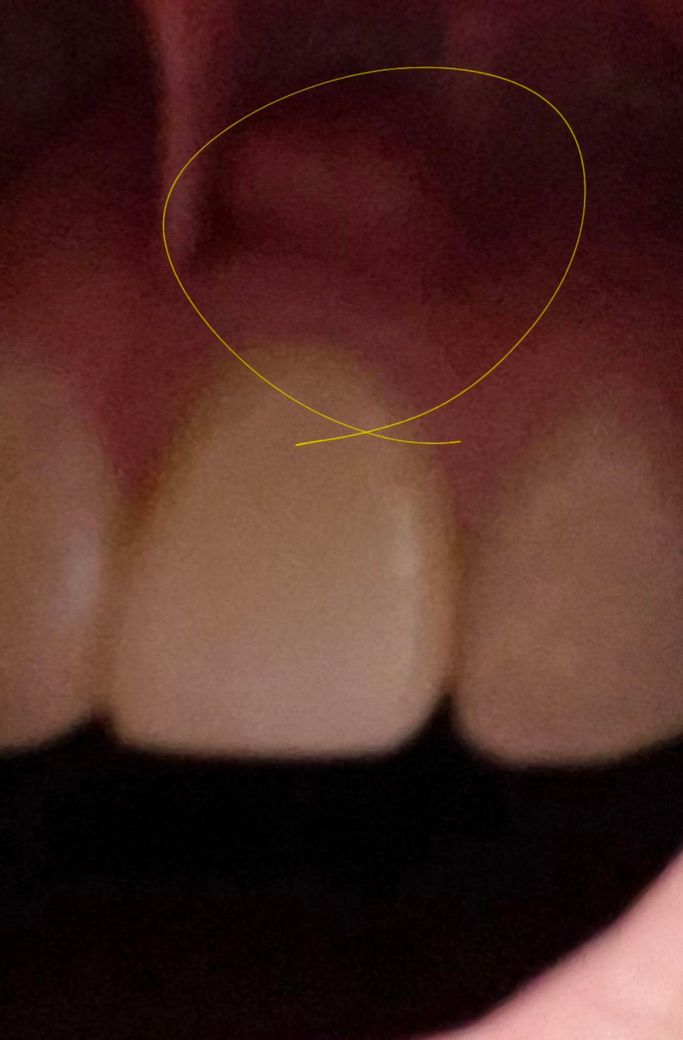

잇몸에 이물감이 있어요 어떻게 해야 하나요?

양치하는데 잇몸에 이물감이 들어서 봤더니 이래서요

뭔지 궁금합니다 큰일인가요? 피가 가거나 하진 않아요

잇몸에 염증이 있어서 그럴 가능성이 높습니다. 치과나, 대학병원 가보심이 좋겠습니다.

잇몸에 염증이 잇어서 그럴수도 잇고 치아 뿌리끝에 염증이 잇어서 그럴수도 잇으니 치과에 가셔서 검진을 받아보세요.

물혹의 양상인데 대학병원급 치과가서 조직검사가 필요한 상황일 수도 있습니다 바로 가보세요